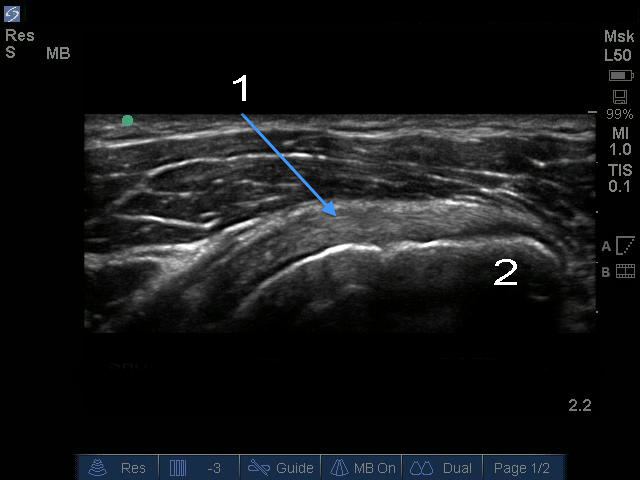

肩部肩胛下肌腱纵轴图像

肩胛下肌

小结节